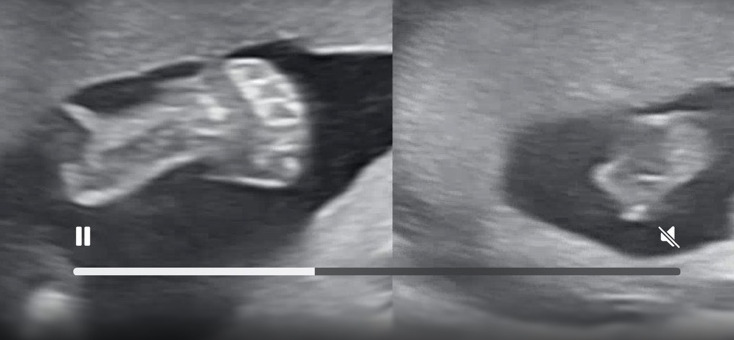

너무 귀여운 손바닥 어쩔 거냐구!!

정확하게 5개!!

우리 토리손 너무 귀엽다...

우리 토리 얼굴 공개~

항상 얼굴 가리고 있었는데 오늘은 보여줬다.

아빠를 닮아 팔 포즈가 가드 올린 거까지 똑같네

내 새끼 ㅎㅎ

울 아기 벌써 이쁘네

우리 토리 발

밤에 수영을 많이 하는지 슈슝 하는 느낌이 든다.

요렇게 작은 발로 슈슝 하고 있었다고 생각하니 너무 기특해,,